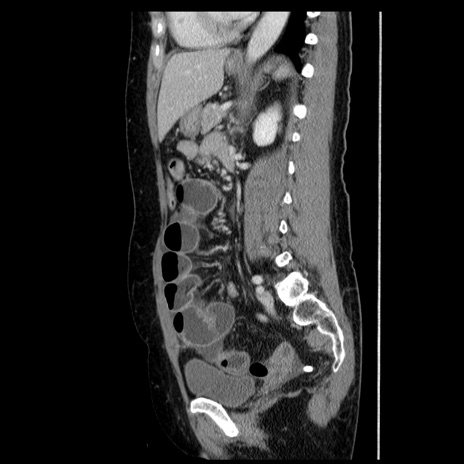

横断像

冠状断像